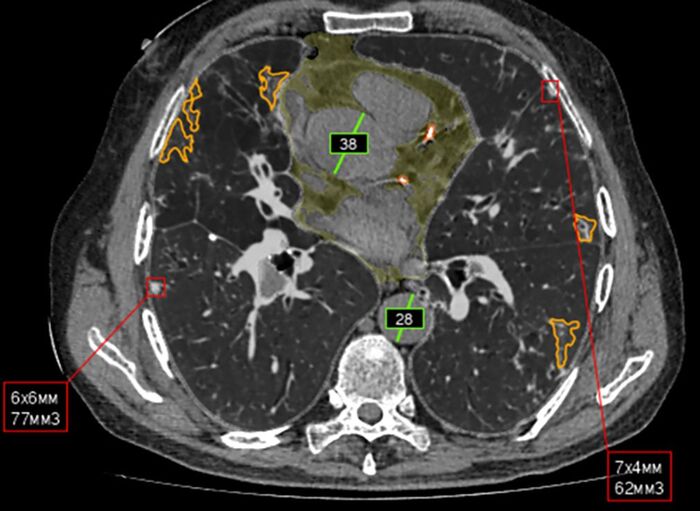

Начиная с 2020 года и по сегодняшний день этот путь прошли уже более 50 сервисов ИИ, которые могут найти признаки рака легкого, пневмонии, плоскостопия, рака молочной железы, инсульта, аневризмы аорты и других заболеваний.

Совсем недавно в Москве заработал новый ИИ-сервис для диагностики заболеваний головного мозга. На снимке КТ нейросеть способна находить признаки ишемического инсульта и кровоизлияний. ИИ может произвести все необходимые измерения за пару секунд, в то время как у врача это займет 2-3 минуты. А скорость в таких ситуациях критически важна и прямо влияет на результаты лечения и последующее качество жизни человека.

Планка требований к качеству разрабатываемых сервисов постоянно повышается. К примеру, в 2020 году ИИ по анализу КТ изображений органов грудной клетки мог определить только пневмонию. Сейчас сервис на аналогичном снимке находит до 12 патологий за раз.